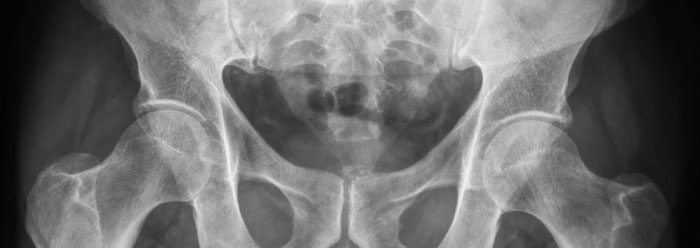

Reinforcing strap structures are found throughout the living world, holding critical biological systems together. Consider human hip structure. The pelvic girdle is comprised of the strongly interconnected bones ilium, ischium, and sacrum. These are gathered into a hoop that serves as the ideal anchoring structure for the thoracic trunk to the legs. During walking or running, more than the weight of the whole body is distributed over the breadth of this biological belt. Specific ligaments and tendons attach to points on the pelvic girdle, making bipedal locomotion not just operable, but efficient.